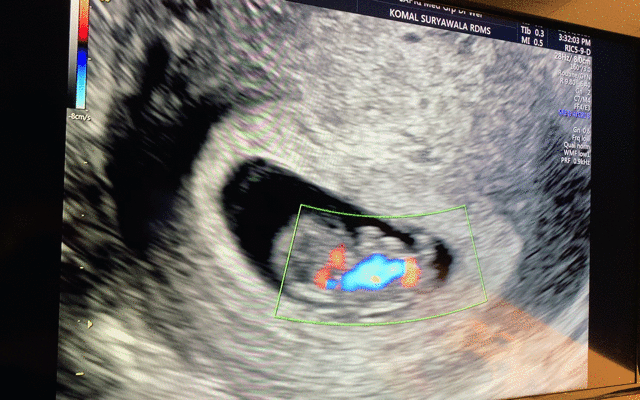

그렇게 튼튼이 모습을 별 설명 없이 보여주셨는데, 움직이길래 '움직인거에요?' 했다. 그러고나서는 감격에 벅차 눈물이 차올랐.. 다기 보다는, '오, 잘 살아있구나' 하는 생각이 들었다. 남편도 보아하니 감격보다는 신기함이 더 큰 것 같았다. 나중에 지나고나서 물어보니, SF 영화에서 보는 외계인 검사 장면ㅋㅋㅋㅋ-_- 같았다고 한다. 아기는 주수에 맞게 잘 크고 있다고 했다. 그리고나서 보여주신 아기 심장 뛰는 모습! 이때 '열심히 자라주고 있구나!' 하는 생각과 함께 책임감이 들면서 조금 뭉클했다. 우리는 이렇게 심장 소리는 듣지 못하고, 보기만 했다. :)

혈액, 소변, 혈압 등 기본 검사를 마치고, 다시 초음파실에 들어가 Judy Wei 선생님에게 진료를 받았다. 문답하면서 기본적인 사항 확인하시고, 아래도 들여다 보시고, 가슴을 조금씩 눌러가면서 멍우리가 있는지도 확인하셨다. 아기는 건강한데, 자궁 경부쪽에 조금 출혈이 있단다.아기도 잘 자라고 있고, 밖으로 비치지는 않는 걸 보니 흡수되고 있어 괜찮은 것 같지만 (나는 착상혈은 커녕 아무 출혈이 없었다.), 혹시 피검사 결과 프로게스테론 수치가 낮을 수도 있으니, 결과 보기 전까지 출혈이 있는 경우를 대비해 질정제 프로게스테론(vaginal progesterone)을 처방한다고 하셨다. (12주차가 되기 전까지 출혈이 있으면 사용하고, 아니면 안해도 된다고 하셨는데, 나는 결국 쓰지 않아도 되었다.)